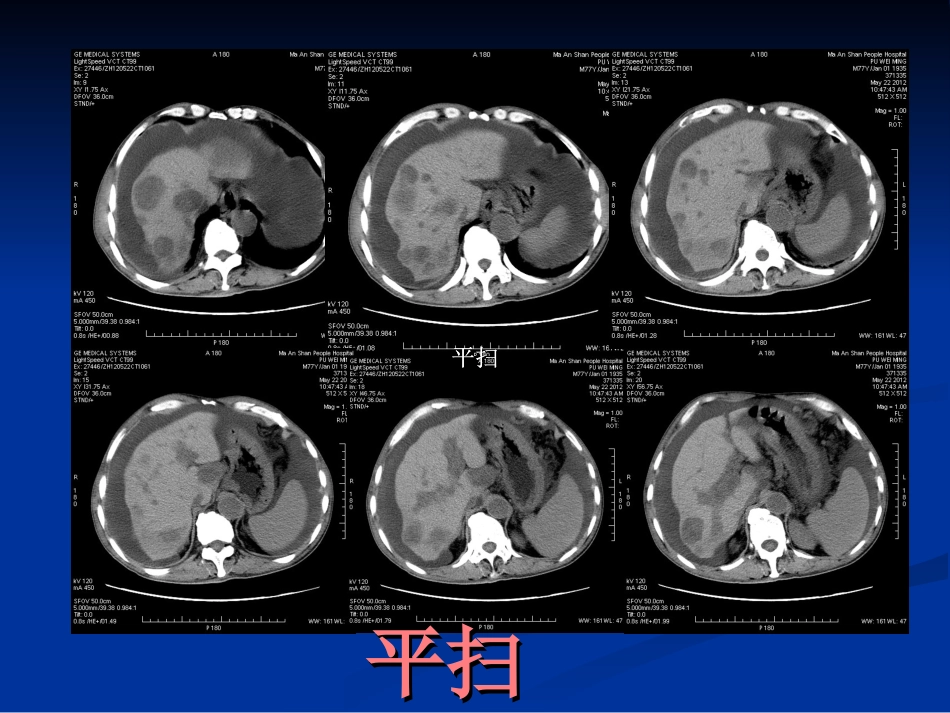

AFPAFP阳性胃癌阳性胃癌马鞍山市市立医疗集团市人民医院马鞍山市市立医疗集团市人民医院舒荣宝舒荣宝2012-7-132012-7-13于解放军于解放军8686医院医院病史摘要病史摘要:患者男,:患者男,7777岁,工人。近岁,工人。近11月来感腹胀、少月来感腹胀、少尿,双下肢浮肿,病程中纳差、睡眠欠佳。无反酸、嗳气、尿,双下肢浮肿,病程中纳差、睡眠欠佳。无反酸、嗳气、呕血、黑便史。既往无乙肝史。体检呕血、黑便史。既往无乙肝史。体检::贫血貌,腹部平软,贫血貌,腹部平软,全腹无压痛及反跳痛,未及异常包块,肝、脾肋下未及。全腹无压痛及反跳痛,未及异常包块,肝、脾肋下未及。移动性浊音(移动性浊音(++)),,双下肢凹陷性水肿。双下肢凹陷性水肿。实验室检查:实验室检查:化学发光法化学发光法::甲胎蛋白(甲胎蛋白(AFPAFP)>)>1000Iu/m1000Iu/mLL(正常范围:(正常范围:0-5.8Iu/mL0-5.8Iu/mL),癌胚抗原(),癌胚抗原(CEACEA):):5.5.62ng/ml62ng/ml(正常范围:(正常范围:0-3.4ng/ml0-3.4ng/ml)),,神经特异性烯醇神经特异性烯醇化酶(化酶(NSENSE)):59.29ng/ml:59.29ng/ml(正常范围:(正常范围:0-16.3ng/m0-16.3ng/mll),),,ESR:28mm/h,ESR:28mm/h。肝功能:干式法:谷丙转氨酶。肝功能:干式法:谷丙转氨酶((ALTALT)):11U/L,:11U/L,碱性磷酸酶(碱性磷酸酶(AKPAKP)):127U/L,:127U/L,血血清胆碱酯酶(清胆碱酯酶(cholinesterasecholinesterase):):3448U/L(3448U/L(4300-1054300-1050000U/LU/L).).白蛋白:白蛋白:29g/L29g/L。肾功能检查未见异常。血常。肾功能检查未见异常。血常规:血红蛋白:规:血红蛋白:8.2g/L8.2g/L。。HBsAg(HBsAg(--))。。平扫平扫平扫平扫平扫平扫动脉期动脉期动脉期动脉期静脉期静脉期静脉期静脉期实质期实质期实质期实质期冠状位冠状位重建重建三维曲面重建三维曲面重建结果与讨论结果与讨论胃镜及病理:胃镜及病理:食管中下段及胃底见曲张的食管中下段及胃底见曲张的静脉,表面见红色征。胃角部局限隆起,静脉,表面见红色征。胃角部局限隆起,形态不规则,胃角及胃窦见多发溃疡。病形态不规则,胃角及胃窦见多发溃疡。病理:瘤细胞大,异型性明显,细胞呈髓样、理:瘤细胞大,异型性明显,细胞呈髓样、条索样排列,血供丰富,免疫组化:条索样排列,血供丰富,免疫组化:AFPAFP弱阳性表达。胃体黏膜中弱阳性表达。胃体黏膜中--低分化腺癌。胃低分化腺癌。胃窦黏膜重度慢性浅表性炎,肠化(窦黏膜重度慢性浅表性炎,肠化(++++)。)。HPHP((--)。)。病理诊断:病理诊断:AFPAFP阳性胃癌阳性胃癌除生殖细胞肿瘤和原发性肝细胞癌外,较多的肿瘤能除生殖细胞肿瘤和原发性肝细胞癌外,较多的肿瘤能产生产生AFPAFP,其中以胃癌较常见,在血清和,其中以胃癌较常见,在血清和//或胃癌或胃癌组织中可以检测出组织中可以检测出AFPAFP,称为,称为AFPAFP阳性胃癌阳性胃癌((alpha-fetoprotein-producinggastricalpha-fetoprotein-producinggastriccarcinomacarcinoma,,AFPGCAFPGC)。其中具有腺癌和肝细胞)。其中具有腺癌和肝细胞癌样分化者称之为胃肝样腺癌(癌样分化者称之为胃肝样腺癌(HepatoidHepatoidAdenocarcinomaofthestomachAdenocarcinomaofthestomach,,HASHAS),),发病率发病率5.1%-15%5.1%-15%左右。其临床病理学特征与普通左右。其临床病理学特征与普通型胃癌有较大不同,特点是好发于中老年男性,更易型胃癌有较大不同,特点是好发于中老年男性,更易发生肝转移和早期淋巴道转移,具有明显的侵袭性和发生肝转移和早期淋巴道转移,具有明显的侵袭性和恶性生物学行为。恶性生物学行为。IshikuraIshikura解释解释AFPAFP的产生是由于胃和肝的产生是由于胃和肝都是来自胚胎发育中的前肠。一些原发性都是来自胚胎发育中的前肠。一些原发性胃癌由于组织分化异常,向肝细胞方向分胃癌由于组织分化异常,向肝细胞方向分化,产生大量的化,产生大量的AFPAFP。。AFPAFP是免疫抑制是免疫抑制因子,机体免疫力受抑制后使癌细胞生长因子,机体免疫力受抑制后使癌细...